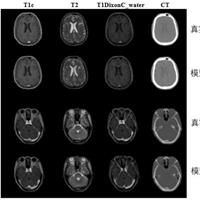

本发明涉及基于多模MRI同步生成的伪CT合成方法,属于医学图像处理领域。该方法将单个模态MRI作为输入,同时输出多个其余模态MRI和伪CT,具体步骤包括:获取单个模态MRI,输入预设的生成器,该生成器由一个共享编码器和J个解码器构成;首先获取前J‑1个解码器生成的同期多个模态的MRI,并将共享编码器和前J‑1个解码器的中间层特征融合,以获得融合特征;将第J个解码器和融合特征进一步融合,获得伪CT图像,J为自然数。本发明能够实现一对多的多...